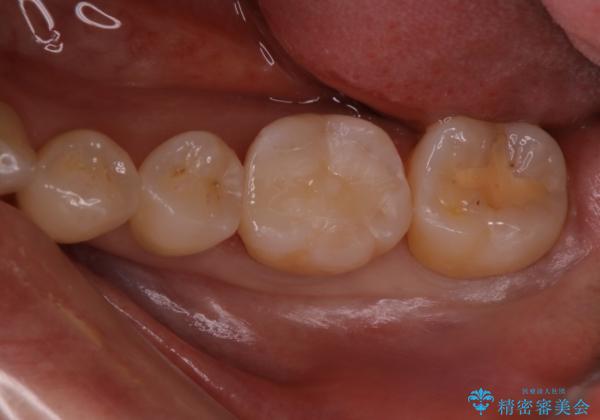

定期検診で虫歯発見。セラミック治療

まずは虫歯をしっかりと取る事が大切です。

虫歯をとった後は、削った形に型を取る事で隙間なく歯にあった被せ物ができてきます。